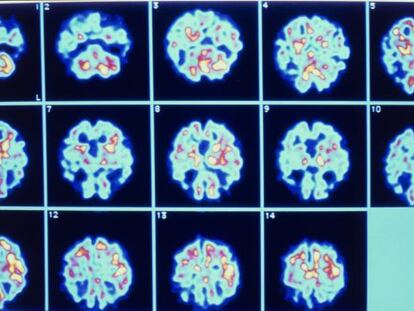

El incremento de la esperanza de vida incrementará los casos en los países en vías de desarrollo Los expertos creen que puede convertirse en el principal desafío sanitario y de asistencia social